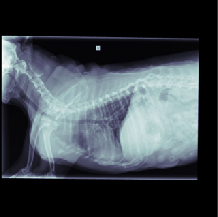

The data for this work consists of 390850 X-ray images, taken from 98660 veterinary sessions. These images were annotated by radiologists for over 41 diseases in a multi-label fashion, and are feedback from the usage of the RapidRead tool. Additionally, we have a dataset of 800 images with high-quality annotations, where the annotations were performed by 12 radiologists collaborating on each image. A sample of these X-ray images is shown in Figure 2.

This section presents visualizations of the Vision Transformer (ViT) attention maps. The ViT used is specific to lung diseases, and the attention maps are shown for patients with the positive label ’Pulmonary Mass’. The input to the ViT is a concatenated feature map, and the X-ray images have been mapped and displayed with the same concatenation and transformations applied to the augmented feature maps.

The attention maps show that the ViT focuses on the thorax region where the lungs are located, as expected. The results also demonstrate that the ViT remains focused on the thorax area even with different contexts in the X-ray images. This highlights the robustness of ViTs.